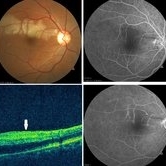

BRAO with CRVO (1 file)

BRAO with CRVO (1 file)